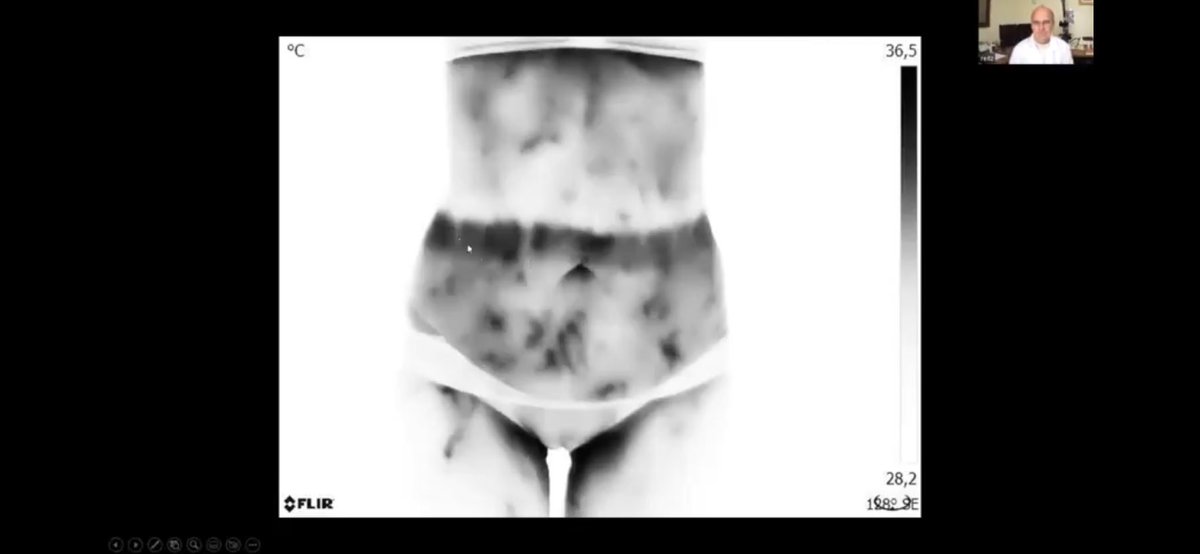

تخثرات دموية وجلطات في منطقة البطن لمطعمين بثلاث و اربع جرعات. 5️⃣